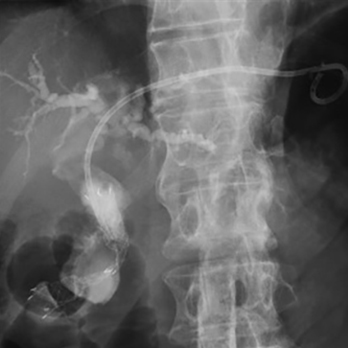

内視鏡的逆行性胆管膵管造影(ERCP)・超音波内視鏡(EUS)による高度な診断治療

胆管炎・胆嚢炎・閉塞性黄疸に対するERCP・EUSによる胆道ドレナージ術・経皮経肝的胆道ドレナージ術(PTBD・PTGBD)

胆管狭窄・膵管狭窄・悪性胃十二指腸狭窄に対する内視鏡的拡張術・ステント留置術

胆管結石・膵石に対する内視鏡的結石除去術

経口胆管鏡と電気水圧衝撃波結石破砕装置(EHL)による胆管結石破砕術

悪性肝門部胆管狭窄に対する

内視鏡的インサイドステント留置術

内視鏡的メタルステント留置術

悪性遠位胆管・十二指腸狭窄に対する